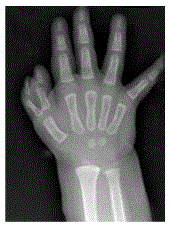

Mulher, 33 anos, com radiografia do punho direito mostrando esclerose do semilunar sem colapso, altura carpal mantida e ângulo escafolunar de 50 graus.

Considerando o diagnóstico de doença de Kienbock, podemos classificar como estágio: